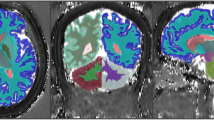

To estimate in-vivo brain relaxometry values, regions of interest (ROI) were drawn directly over T1 MRF relaxometry maps using the ITK-SNAP software Version 3.8 [39]. ROIs were then copied to MRF T2 maps. Clinical pre- and post-contrast MRI images were used as reference for all 15 study patients. ROIs were drawn to include the meningioma as well as normal structures that included the centrum semiovale (CS), thalamus, contralateral white matter (CWM) and caudate head (CH). The rationale in selecting normal brain structures that are both on deep gray matter and white matter is to compare how the MRF numbers we described on those structures are in accordance to more established literature descriptions on relaxometry in these same structures. All ROI were reviewed by board-certified neuroradiologists prior to finalization. Figure 2 illustrates ROIs used to quantify these regions. If the meningioma crossed the midline, then the CWM ROI in the hemisphere opposite to the epicenter of the lesion was chosen. In those patients who had more than one meningioma, the location of the CWM ROI was chosen in the hemisphere opposite the largest lesion.

MRF-derived T1 relaxation maps from the same subject. a Depicts ROI drawings in the (1) meningioma and (2) contralateral white matter (CWM). b Illustrates the ROIs used to encompass the caudate head (CH) (3) and thalamus (4). The grayscale is calibrated in milliseconds (ms), shown to the right of the respective relaxation maps